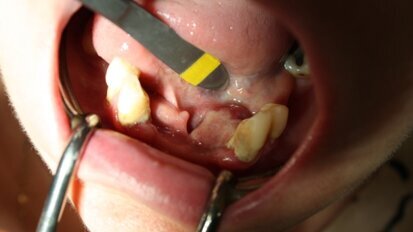

Jednoetapowe hydrokinetyczne podniesienie dna zatoki szczękowej z wykorzystaniem kwasu hialuronowego

Autorzy przedstawiają przypadek pacjentki z zaawansowanym zanikiem poziomym kości szczęki, u której w celu podniesienia dna zatoki szczękowej ...